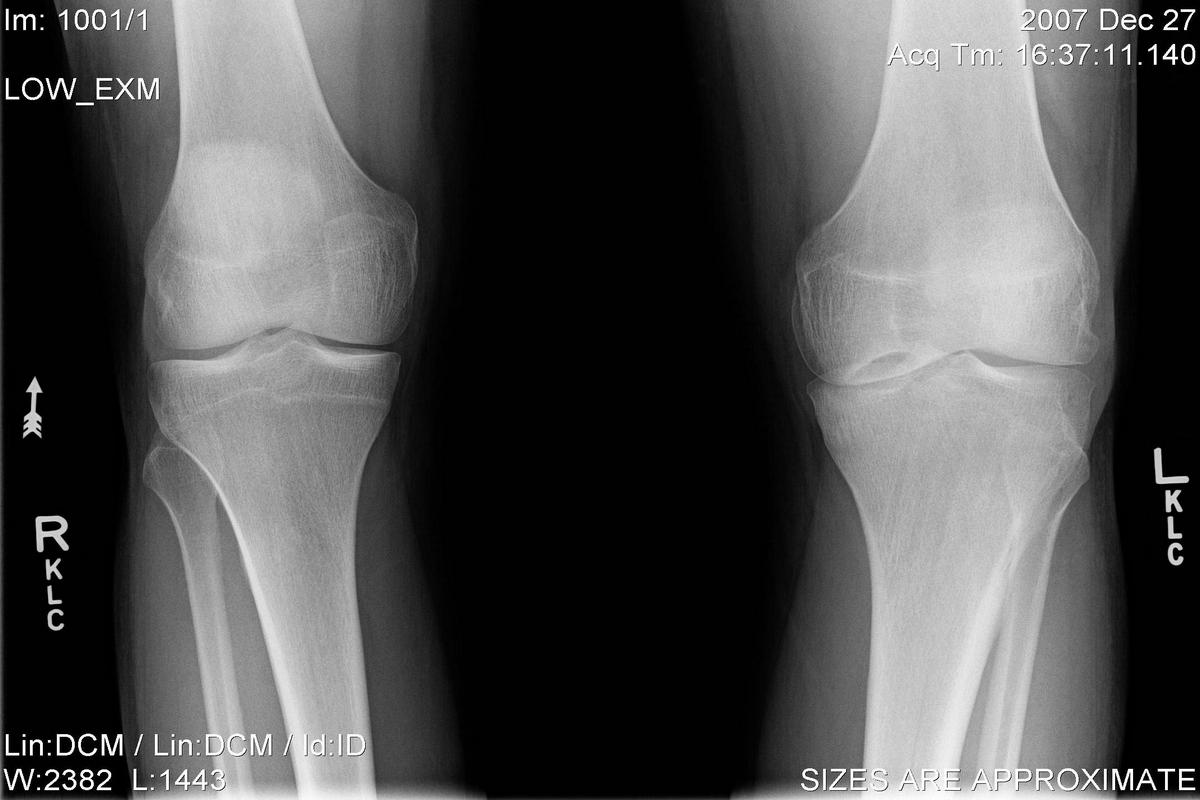

Η διάγνωση βασίζεται αρχικά στην κλινική εξέταση, με εκτίμηση της κινητικότητας, της ευαισθησίας και της σταθερότητας του γόνατος. Ο απεικονιστικός έλεγχος παίζει καθοριστικό ρόλο, με τη μαγνητική τομογραφία (MRI) να αποτελεί τη μέθοδο εκλογής, καθώς απεικονίζει με ακρίβεια το μέγεθος, το βάθος και την εντόπιση της βλάβης.